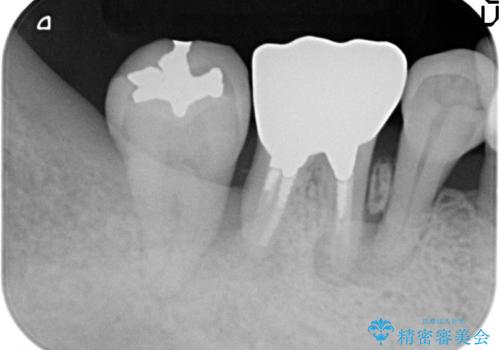

- 歯周病により歯を支える骨がなくなってしまっていたため、歯を取り除き、インプラントにて回復します。

歯周病でぐらぐらになってしまった奥歯を抜歯し、残る骨の高さを鑑みてショートインプラントを選択しました。

インプラントの種類:Bicon